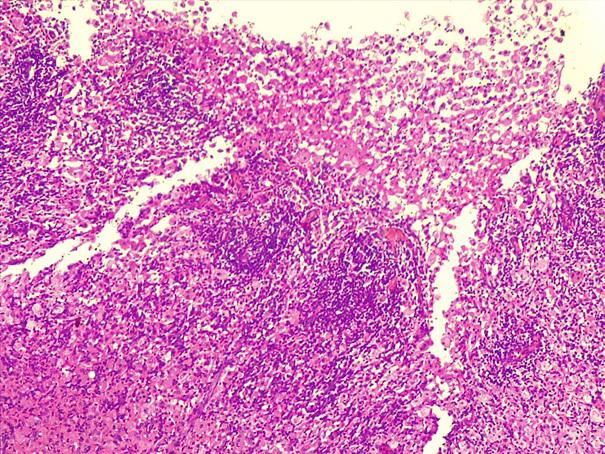

*Case 2 : Dr Rimamskep Ifusumu/ Prof Modupeola Samaila

email: mamak97@yahoo.com

Clinical details: Female, 38years, Ovarian mass ?

Please, consult the virtual slides of Case 2 below.